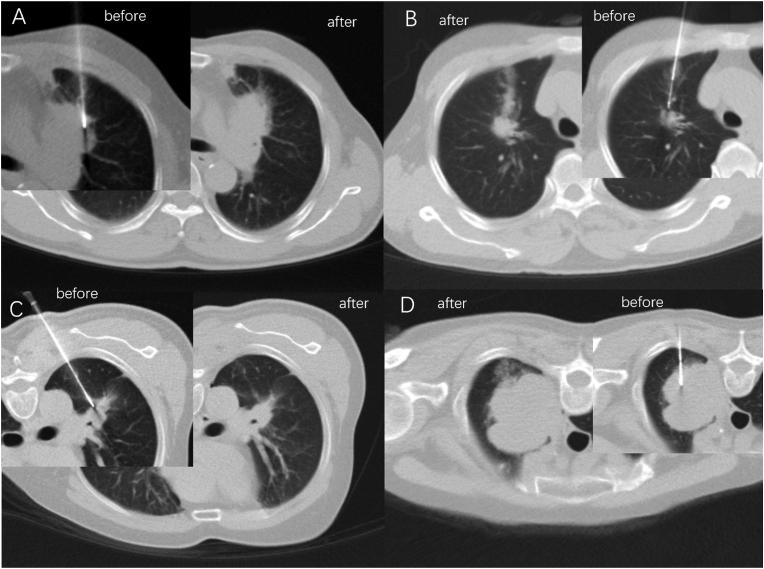

低剂量与优化长度计算机断层扫描(CT)扫描在CT引导下经皮肺穿刺活检肺结节中的价值

To investigate the value of application of low-dose and optimized length CT scan on puncture results, complications and patients' radiation dosage during CT-guided percutaneous biopsy of pulmonary nodules (PTNB).

METHODS

A total of 231 patients with PTNB under CT guidance were collected. Low dose scanning utilized tube current of 20 mA as compared with 40 mA in conventional dosage. Optimized length in CT is defined as intentionally narrowing the range of CT scanning just to cover 25 mm (5 layers) around the target layer during needle adjustment. According to whether low-dose scans and optimized length scans techniques were utilized, patients were divided into three groups: conventional group (conventional sequence + no optimization), optimized length group (conventional sequence + optimized length), and low-dose optimized length group (low dose sequence + optimized length). The ED (effective dose), the DLP (dose length product), the average CTDIvol (Volume CT dose index), total milliampere second between subgroups were compared.

RESULTS

Compared with the conventional group, ED, intraoperative guidance DLP, total milliseconds and operation time in the optimized length group were reduced by 18.2% (P=0.01), 37% (P=0.003), 17.5% (P=0.013) and 13.3% (P=0.021) respectively. Compared with the optimized length group, the ED was reduced by 87%, preoperative positioning, intraoperative guidance and postoperative review DLP were also reduced by 88%, total milliampere second was reduced by 79%, with an average CTDIvol was reduced by 86%, in the low-dose optimized length group (P<0.001 for all).

CONCLUSION

Optimizing the length during CT scanning can effectively reduce the intraoperative radiation dose and reduce the operation time compared with conventional plan; low-dose and optimized length CT scan can further reduce the total radiation dose compared with optimized length group with no differences on intraoperative complications, biopsy results and operation time.